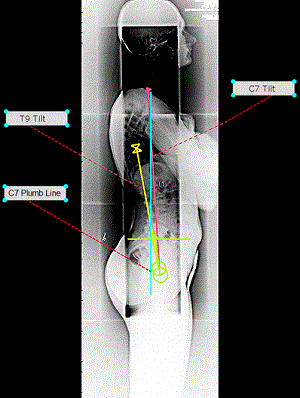

Sau đó, bác sĩ cũng có thể đo và vẽ các giá trị sau:

- T9 Tilt

- C7 Tilt

- C7 Plumb Line

Phần mềm phẫu thuật 3D Spine cung cấp tất cả dữ liệu quan trọng mà bác sĩ cần để lập kế hoạch phẫu thuật nhanh chóng, hiệu quả.